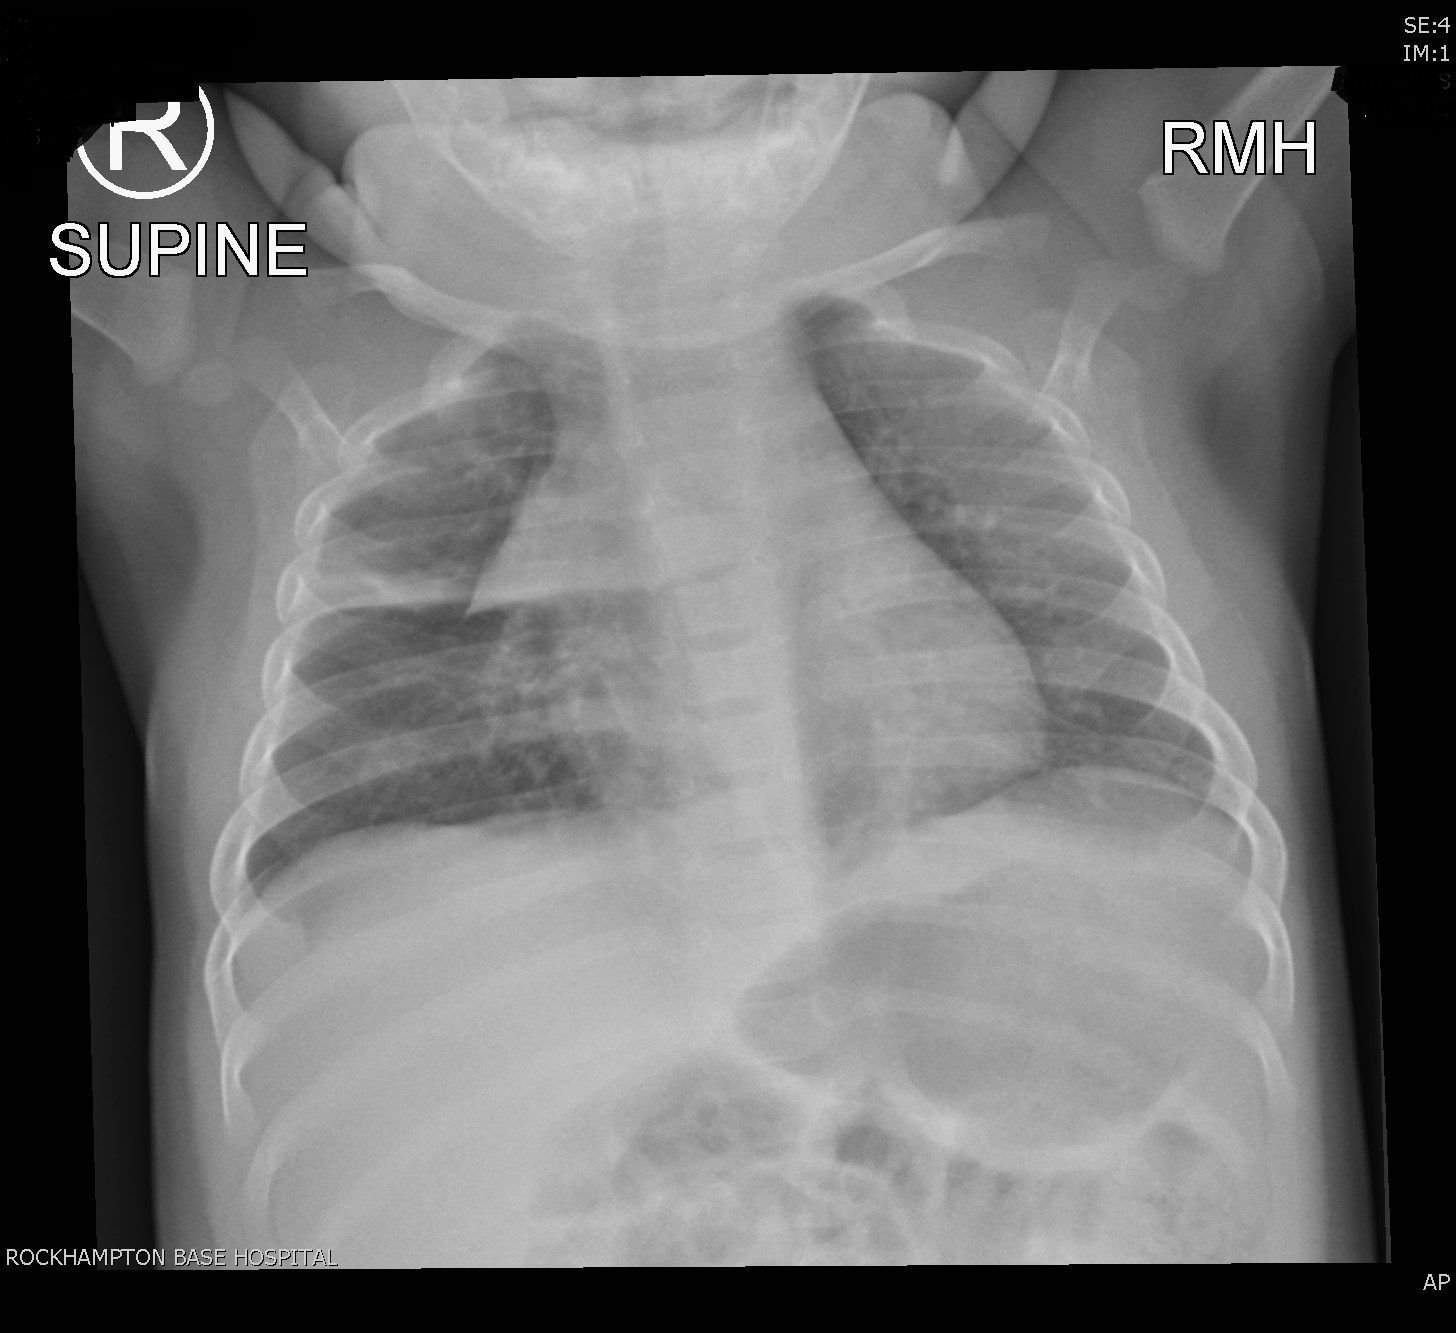

FINDINGS

Normal cardiomediastinal contour. Note the normal appearing thymic shadow.

Lateral to this in the right lung mid zone is patchy atelectasis and consolidation involving the right upper lobe. This is likely infectious in nature. Remaining lungs and pleura are clear.